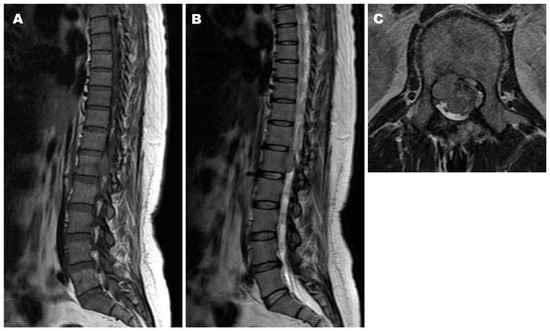

2.2. Case 2

| Present cases | 40/F | T12-L1 | 3 | GTR | SFT grade II | 228 | Local recurrence at 72 mos | ||